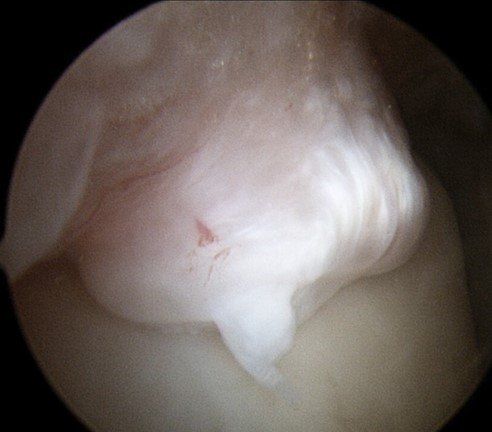

When symptoms persist, ankle arthroscopy is used to "clean-out" the ankle. Occasionally, the ankle needs to be opened to access deep scar tissue or very large spurs and bone fragments.

This procedure removes:

- scar tissue and inflammation (synovitis)

- bone spurs (see images below)

- loose bone and cartilage fragments.